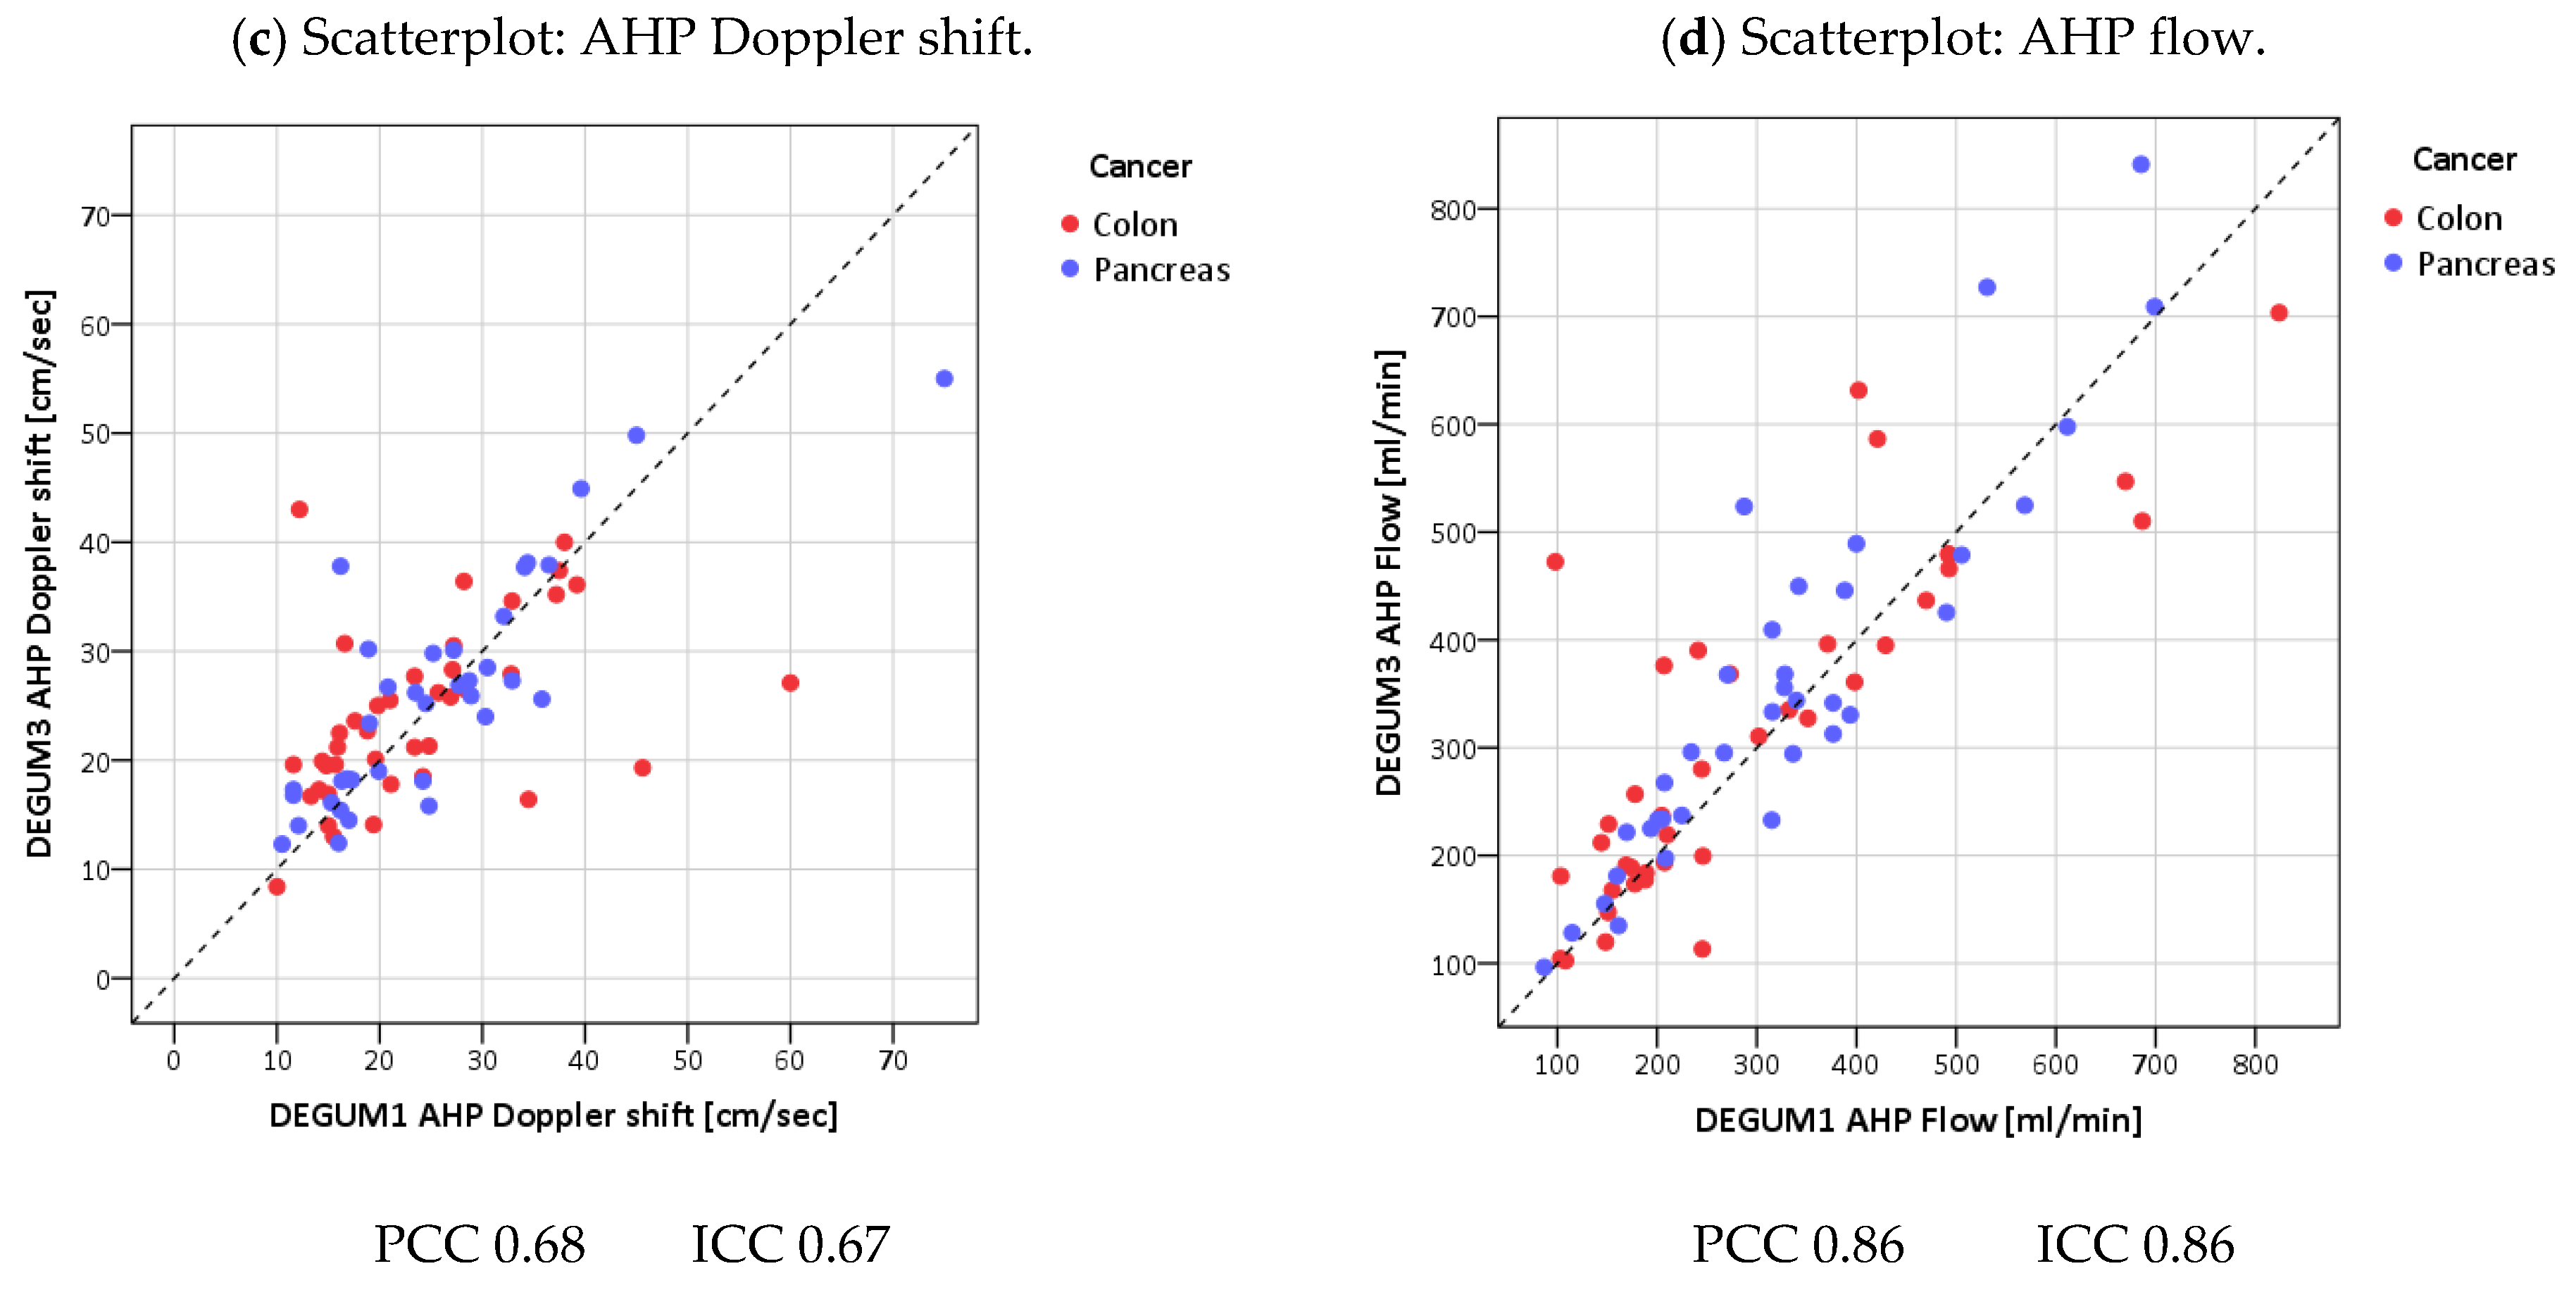

| Parameter | Diameter [mm] | Insonation Angle | Doppler Shift [cm/s] | Flow [mL/min] | AHC-DPI |

|---|---|---|---|---|---|

| N | 75 | 60 | 60 | 60 | 60 |

| Mean D1 (SD) | 5.7 (1) | 52.1 (9.2) | 22.1 (7.3) | 579 (240) | 0.4 (0.1) |

| Mean D3 (SD) | 5.8 (0.9) | 48.4 (11.4) | 23.8 (8.1) | 598 (252) | 0.4 (0.1) |

| Mean tot (SD) | 5.7 (0.9) | 50.2 (10.5) | 23 (7.7) | 588 (245) | 0.4 (0.1) |

| Mean Diff (SD) | 0.0 (0.4) | −3.7 (10) | 1.7 (5.7) | 20 (148) | 0.01 (0.06) |

| p(Bias) | 0.50 | 0.002 | 0.008 | 0.30 | 0.55 |

| p(Var) | 0.97 | 0.29 | 0.73 | 0.70 | 0.82 |

| PCC | 0.91 | 0.54 | 0.73 | 0.82 | 0.87 |

| ICC (95% CI) | 0.91 (0.86; 0.94) | 0.51 (0.24; 0.67) | 0.71 (0.55; 0.82) | 0.82 (0.72; 0.89) | 0.87 (0.79; 0.92) |

| MVC | 0.04 | 0.13 | 0.13 | 0.14 | 0.07 |

| B/A Limits | (−0.78; 0.82) | (−23.3; 16.0) | (−9.4; 12.9) | (−270; 310) | (−0.13; 0.12) |